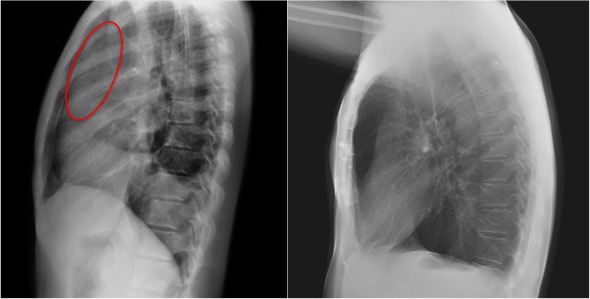

CASO: Pediátrico de más de 2 años tratado por porceso oncológico que ha comenzado con febricula y tos.

Hallazgos:

- Parénquimas pulmonares y silueta cardiomediatínica sin alteraciones significativas. No hay foco neumónico.

- Catéter reservorio subcutáneo con extremo distal en aurícula derecha.

- Resección de la porción anterior de la 6ª costilla. Suponemos que es ahí donde radicaba su proceso de base